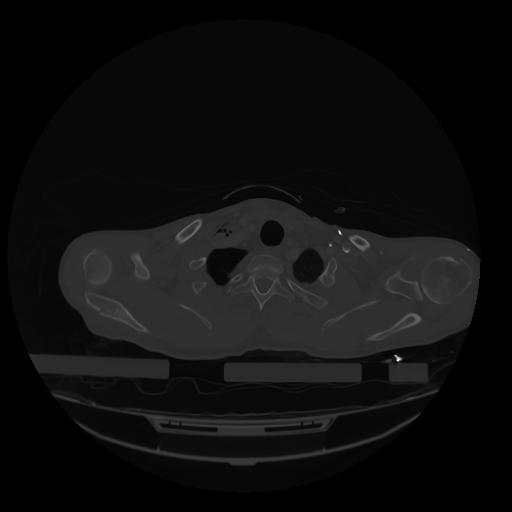

28 CUERPO,CE,Vol,2.0,CUERPO,,